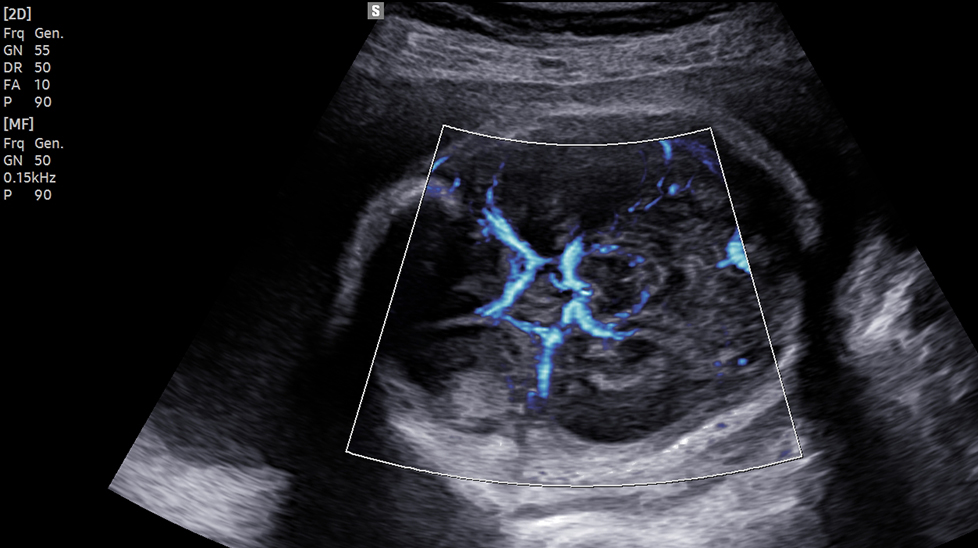

The color imaging performance has been improved to clearly visualize the hemodynamics of the blood flow. A greater sensitivity resulting from new color signal processing and a realistic 3D visualization of blood flow help understand the microcirculatory blood flows, accurate detection of peripheral blood vessels, and volumes of slow blood flows.

LumiFlow™ is a function that visualizes blood flow in three dimensional-like to help understand the structure of blood flow and small vessels intuitively.

MV-Flow™ visualizes microcirculatory and slow blood flow to display the intensity of blood flow in color. It is suitable for observation of microcirculatory blood flow and volume of slow blood flow.

The function uses directional power Doppler technology, enabling you to examine even the peripheral vessels. It displays information on the intensity and direction of blood flow.